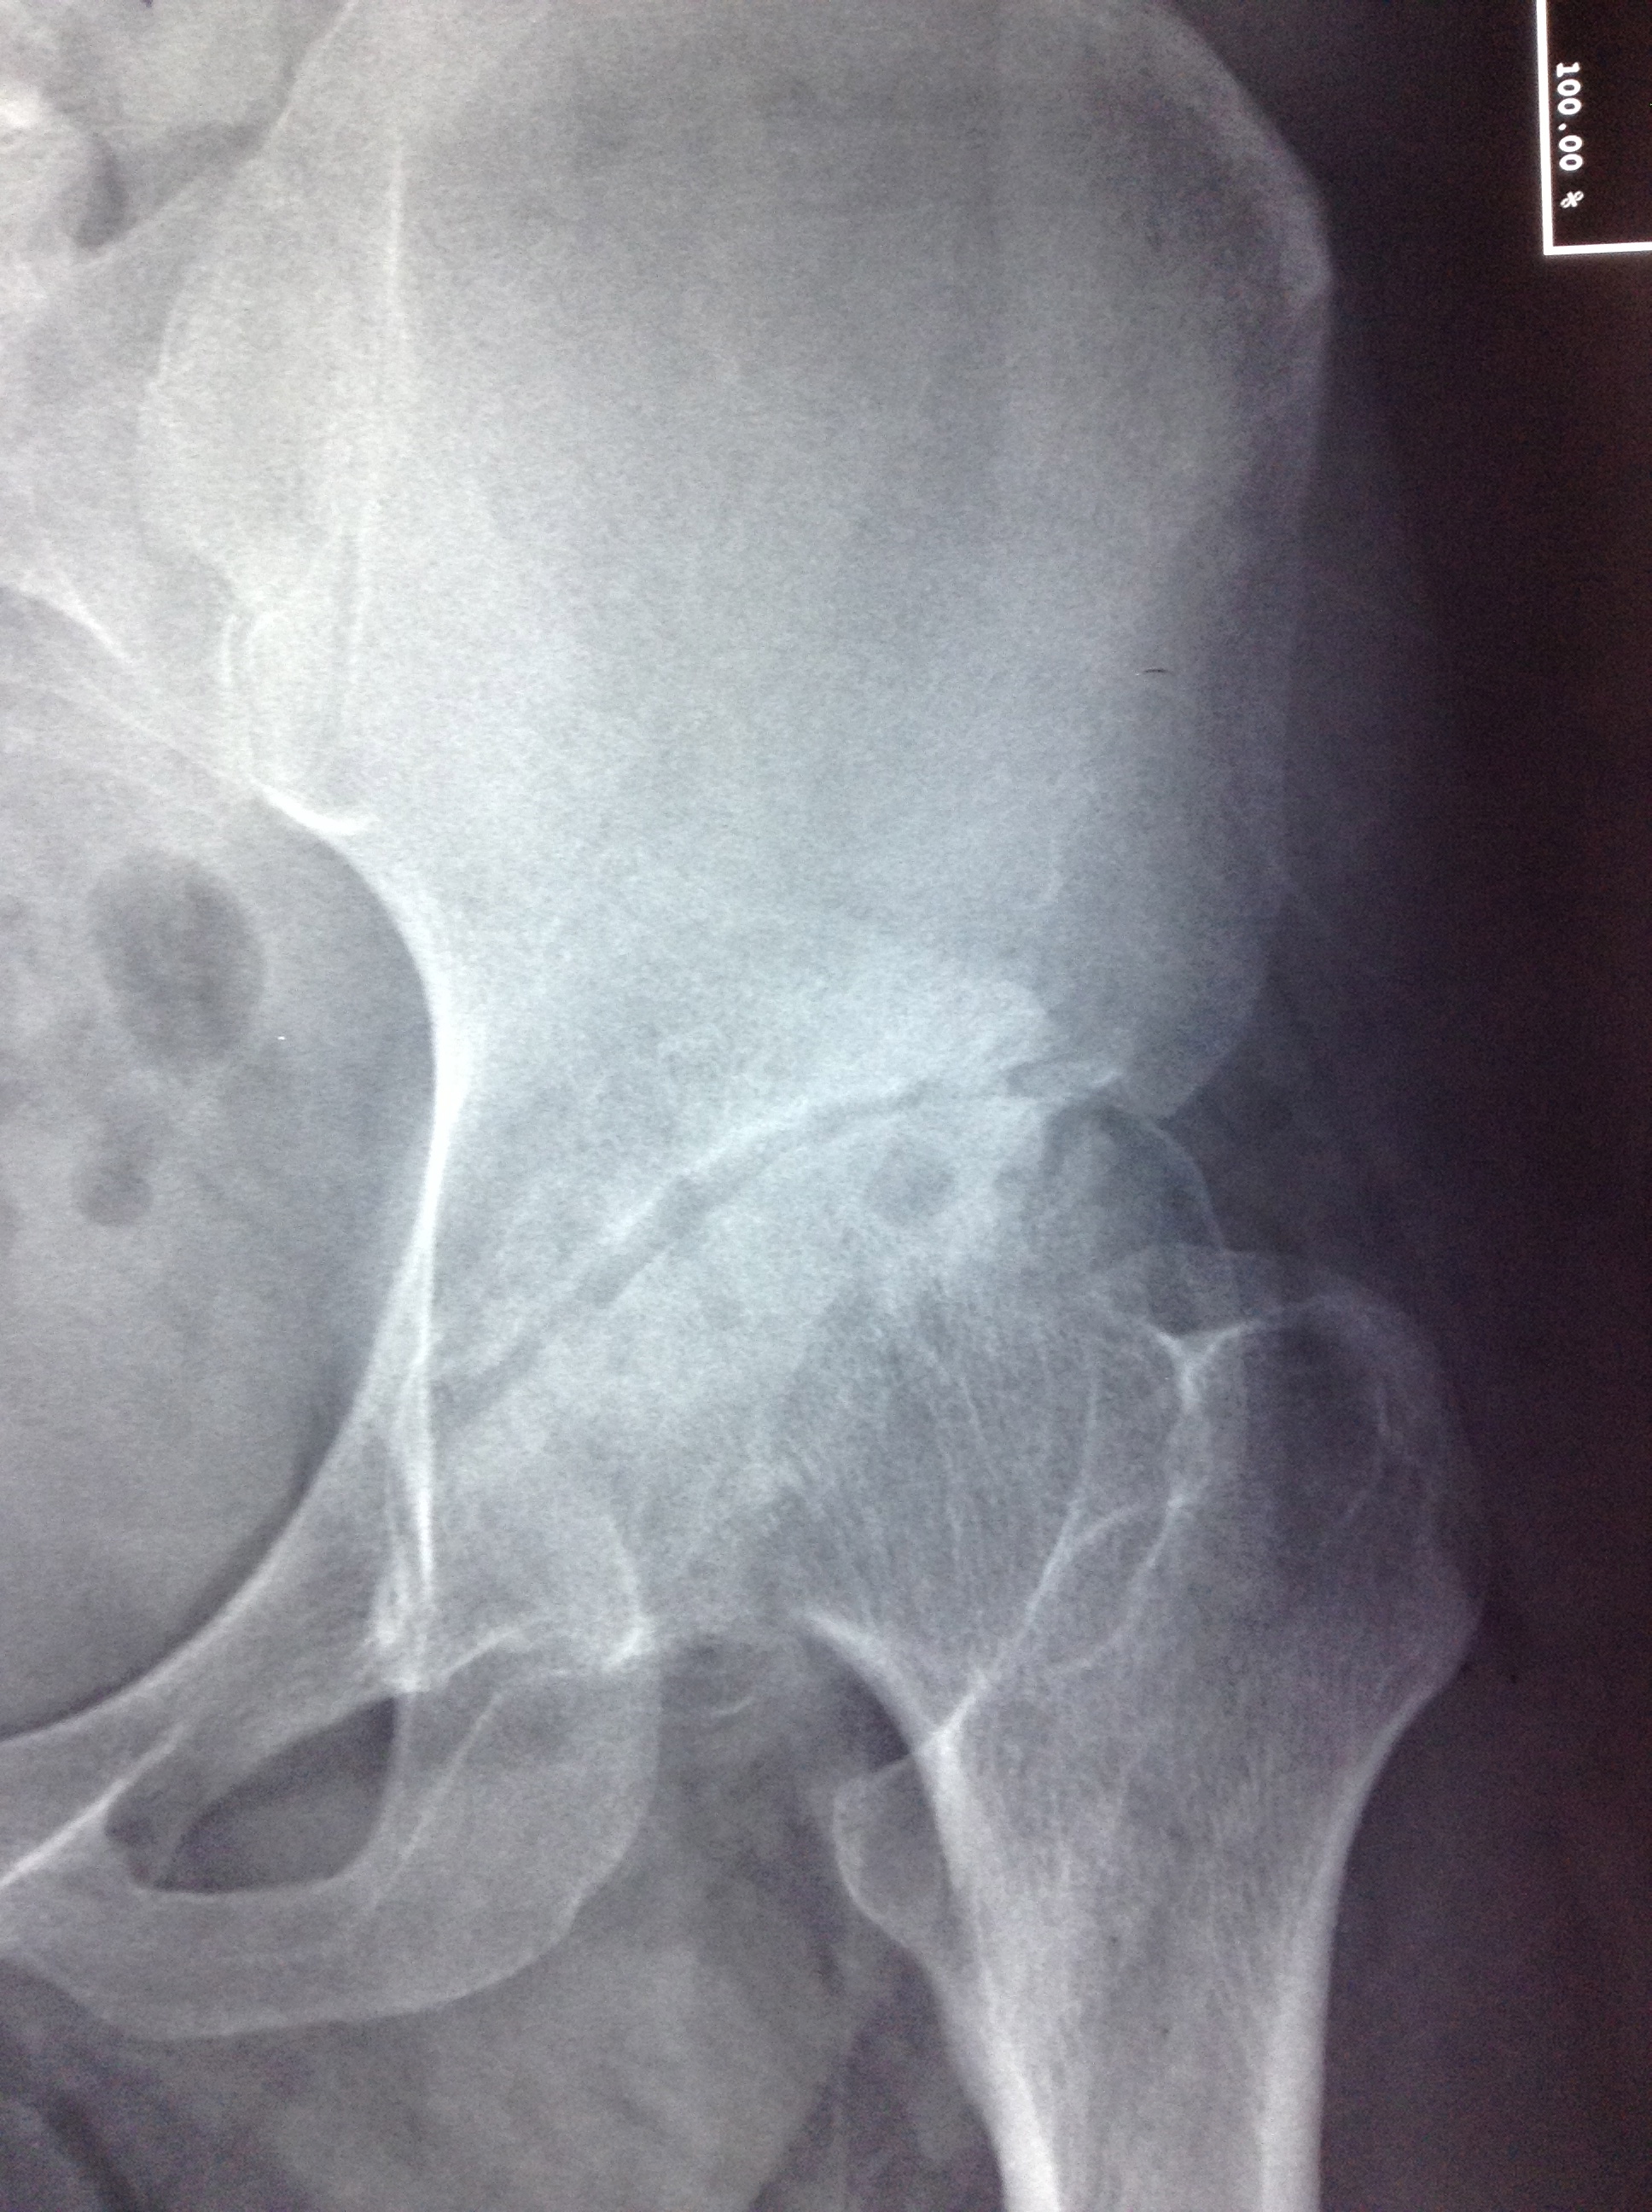

high hip dislocation

• high hip dislocation